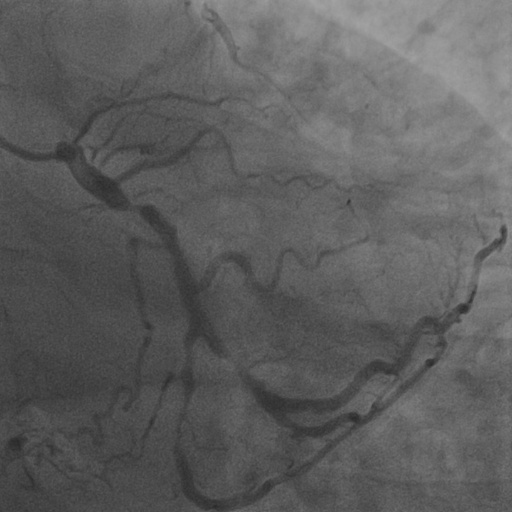

4.1 XACV Dataset

We collect 111 complete records of coronary artery X-ray videos, encompassing the injection, flow through the blood vessels around the heart, and dissipation of the contrast agent. Subsequently, we establish the XACV (X-ray Angiography Coronary Video) dataset. Each video consists of varying numbers of high-resolution coronary artery X-ray images. We invite experienced radiologists to annotate the vascular regions, focusing on one or two frames where the contrast agent is most prominent in each video. The XCAD dataset contains only a single image, and the CADICA video dataset does not provide corresponding ground truth. Therefore, in the following experiments, we conduct all the analyses on our collected XACV dataset and the corresponding GT for each sequence. In Figure 5, we show that compared to other publicly available datasets, XCAD [33] and CADICA [19], our dataset exhibits finer annotations in the vascular regions, providing an advantage for future related tasks. The development and use of our dataset have been approved by our institution’s IRB.